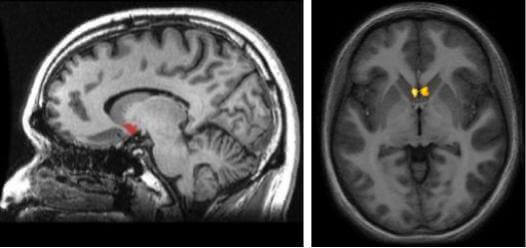

En un estudio de neuromarketing con resonancia magnética funcional, adelantado por Martin Lindstrom y la doctora Gemma Calvert, en 2007, se evidenció que, cuando los fumadores observan las imágenes con advertencias antitabaco, se estimula una zona del cerebro llamada núcleo accumbens. Esta área se activa cuando el cuerpo desea algo muy intensamente.